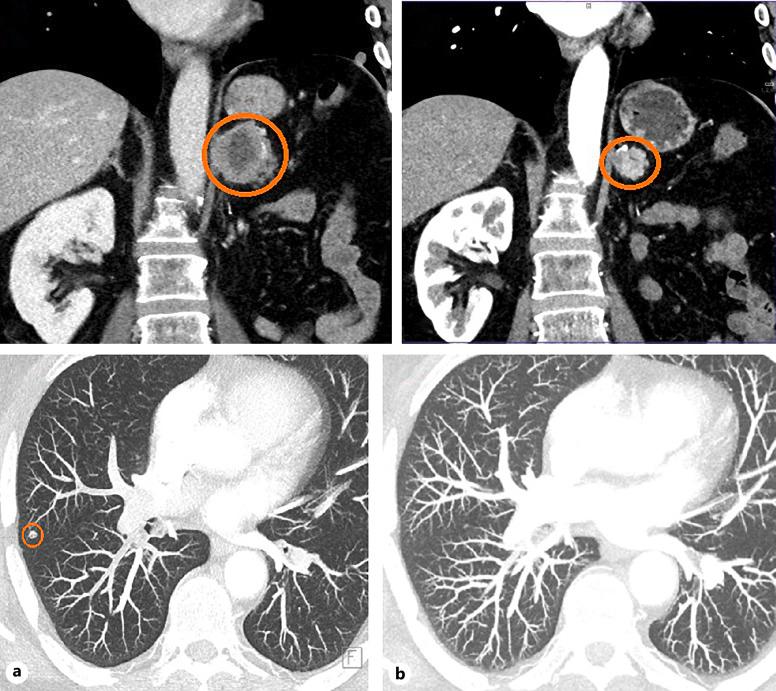

We describe a case of rare irAEs manifested as giant cell temporal arteritis (GCA) followed by severe encephalopathy occurring after continuing immunotherapy in a 66-year-old man with mRCC receiving a combination of ipilimumab and nivolumab in the first line of systemic therapy. GCA occurred 4 months after the initiation of IO and responded promptly to the low-dose prednisone therapy. Four months after the continuation of nivolumab maintenance, the patient was hospitalized due to severe irAE encephalopathy which presented as psycho-behavioral abnormalities and progressive cognitive decline. He was treated with high-dose methylprednisolone which led to complete resolution of the symptoms and IO was permanently discontinued. The patient achieved a durable partial response.

我们描述了一例罕见的irAE病例,表现为巨细胞颞动脉炎(GCA),随后在一名66岁的mRCC男性患者中,在一线全身治疗中接受伊匹木单抗和纳武单抗联合治疗后继续免疫治疗时发生了严重脑病。GCA在IO治疗开始后4个月出现,对低剂量泼尼松治疗迅速产生反应。在继续使用纳武单抗维持治疗4个月后,患者因严重的irAE脑病住院,表现为心理行为异常和进行性认知下降。他接受了大剂量甲泼尼龙治疗,症状完全缓解,IO治疗永久停药。患者获得了持久的部分缓解。